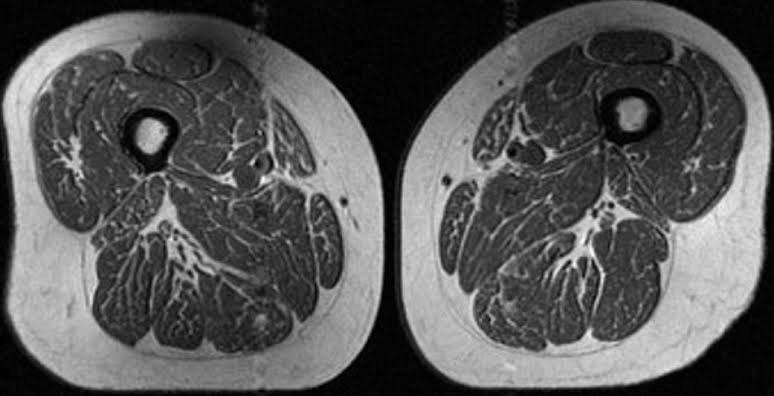

Ultraprocessed foods are turning human thighs into well-marbled steaks

Diets high in ultraprocessed foods create streaks of fat in human muscles that may lead to osteoporosis, a new study found.